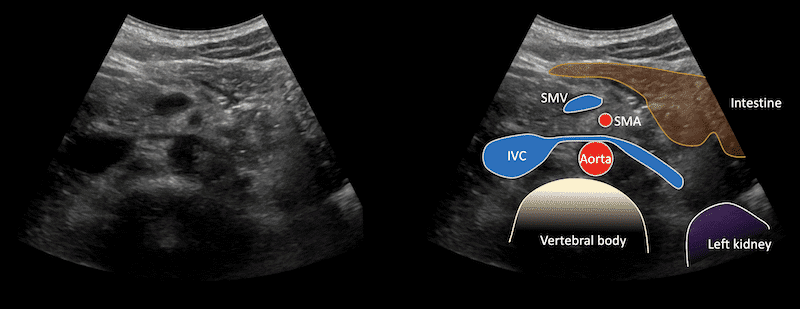

Immagine 4: Vista trasversale dell’epigastrio che mostra la vena renale sinistra.

La vena renale sinistra è visibile mentre viene parzialmente compressa dall’arteria mesenterica superiore contro l’aorta mentre attraversa il rene tra i due, per unirsi alla IVC.